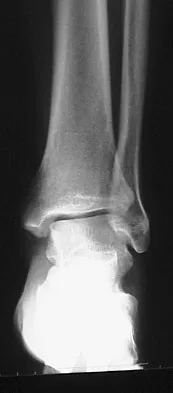

A 57-year-old man has had right ankle pain for the past 10 months following an injury that went untreated. Radiographs are shown in Figures 30a through 30c. Management should consist of

The radiographs reveal a malunited distal fibular fracture with shortening. Because there appears to be an adequate cartilage space within the ankle joint, the role of reconstruction would be to prevent arthrosis and the need for ankle arthrodesis, as well as to decrease symptoms. The treatment of choice is restoration of fibular length, alignment, and rotation with osteotomy plating, and bone grafting as needed. There is no indication for ligament reconstruction of a mechanically stable ankle, and tibial shortening osteotomy will not assist in correcting the deformity. Cast immobilization may assist with improvement of symptoms but will not correct the overall process. Determination of fibular length is best done by comparing the talocrural angle of the injured side with the uninjured side. The goal is to perfectly reduce the talus in the ankle mortise. Marti RK, Raaymakers EL, Nolte PA: Malunited ankle fractures: The late results of reconstruction. J Bone Joint Surg Br 1990;72:709-713. Geissler W, Tsao A, Hughes J: Fractures and injuries of the ankle, in Rockwood CA Jr, Green DP, Bucholz RW, Heckman JD (eds): Rockwood and Green's Fractures in Adults, ed 4. Philadelphia, PA, Lippincott-Raven, 1996, pp 2201-2206.